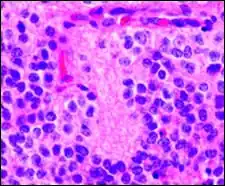

Perivascular pseudorosette

A perivascular pseudorosette consists of a spoke-wheel arrangement of cells with tapered cellular processes radiates around a wall of a centrally placed vessel. The modifier “pseudo” differentiates this pattern from the Homer Wright and Flexner-Wintersteiner rosettes, perhaps because the central structure is not actually formed by the tumor itself, but instead represents a native, non-neoplastic element. Also, some early investigators argued about the definition of a central lumen, choosing “pseudo” to indicate that the hub was not a true lumen but contained structures. Nevertheless, this pattern remains extremely diagnostically useful and the modifier unnecessarily leads to confusion. Perivascular pseudorosettes are encountered in most ependymomas regardless of grade or variant. As such, they are significantly more sensitive for the diagnosis of ependymomas than true ependymal rosettes. Unfortunately, perivascular pseudorosettes are also less specific in that they are also encountered in medulloblastomas, PNETs, central neurocytomas, and less often in glioblastomas, and a rare pediatric tumor, monomorphous pilomyxoid astrocytomas.[2]

Micrograph of perivascular pseudorosettes -

Structure of a perivascular pseudorosette